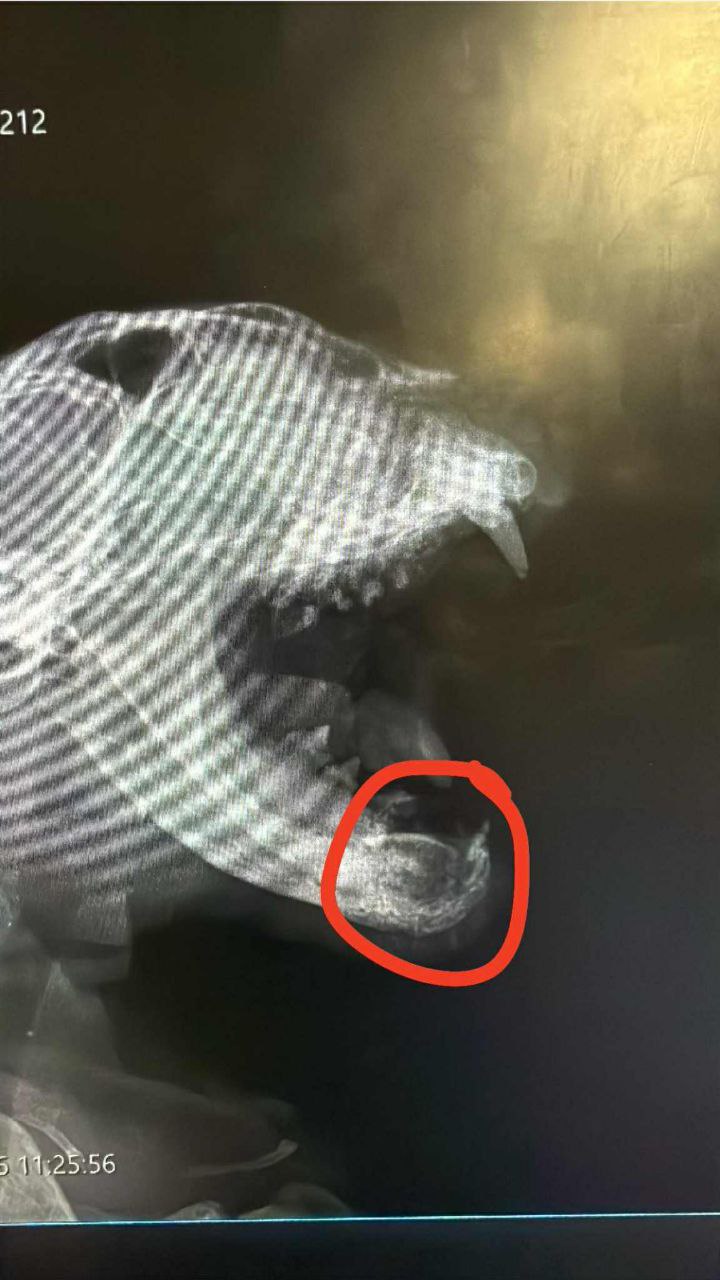

@835780013Вчера ночью нашли бездомного кота, сбитого машиной.

Отвезли его в единственную открытую клинику — Small Animal Hospital (Лимассол).

Были сделаны обследования и анализы (из-за температуры и обезвоживания)

Счёт и фото прилагаю.

Сегодня была проведена операция на челюсть, а также зашит порванный язык.

Глаз " упаковали " и временно зашили.

К сожалению, выяснилось, что котик слепой 😢